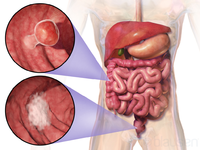

سرطان القولون والمستقيم

مقالة مفصلة: سرطان القولون والمستقيم

| سرطان القولون والمستقيم | ||

| معدل الانتشار | 9.4 مليون (2015)[7] | |

| معدل البقاء 5 سنوات | 65% (الولايات المتحدة)[4] | |

| حالات الوفاة | 832.000 (2015)[6] | |

| عوامل الخطورة | التاريخ العائلي لحدوث سرطان القولون والمستقيم في الأسرة؛ سلائل (پوليپات) polyps أو أمراض الأمعاء الالتهابية. تم ربط وجود طفرات جينية نوعية بداء السليلات الغدومي العائلي familial adenomatous polyposis (الذي يمكنه أن يتحول إلى سرطان القولون) وبسرطان القولون والمستقيم الوراثي غير السليلي. ويزداد خطر الإصابة أيضا عند الذين يعيشون في المدن أو المناطق الصناعية. وتتضمن بقية عوامل الخطورة نقص النشاط البدني والتعرض لمواد كيميائية معينة وتناول الأغذية الغنية بالدهون أو قليلة الألياف. | |

| العلامات المنذرة | وجود دم في البراز؛ أيُّ تغيرٍ في عادات التغوط؛ انزعاج معدي عام، فقدان وزن ليس له ما يبرره. | |

| الكشف والتشخيص | يجب إجراء فحص المستقيم بالإصبع وتحرّي الدم في البراز سنويا لكل شخص يفوق الأربعين عاما؛ تنظير السيني sigmoidoscopy كل 3 ـ 5 سنوات بعد سن الخمسين. وإذا اشتُبِه بوجود أي اضطرابات، يمكن إجراء تنظير القولون واستخدام رحضة (حقنة) الباريوم barium enema (للتمكن من رؤية الأمعاء عند التصوير بالأشعة السينية). ويكون الإنذار prognosis سيئا إذا كانت الأمعاء مسدودة أو مثقوبة أو كانت مستويات مواد واسمة marker substances معينة (مثل المستضد الجنيني السرطاني carcinoembryonic antigen والمستضد الكربوهيدراتي 9-19) في مصل الدم مرتفعة قبل العلاج.

| |

| العلاج | الجراحة لإزالة الورم، وأحيانا يضاف إليها المعالجة الشعاعية أو الكيميائية أو كلتيهما. وقد يتحتم في بعض الحالات فَغْر القولون colostomy (عمل فتحة تصريف فيه). وإذا انتشر المرض إلى العقد اللمفاوية، تصبح المعالجة الكيميائية بالفلوروراسيل fluorouracil مفيدة. وبالنسبة لسرطان المستقيم المتقدم والمتوسط الشدة تستخدم المعالجة الكيميائية المترافقة مع المعالجة الشعاعية، ولعل إزالة النقائل من الكبد جراحيا تطيل بُقيا بعض المرضى.